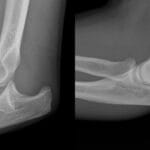

Shoulder fractures

Common shoulder fractures concern the clavicle (collarbone), humerus (upper arm bone), and scapula (shoulder blade) and present with swelling, deformity, bruising, loss of function, and severe pain. Elderly patients tend to fall from standing height and it is often the cause of a fractured shoulder. Alternatively, younger patients tend to get shoulder fractures from high energy injury, such as road traffic accidents or contact sports injuries.